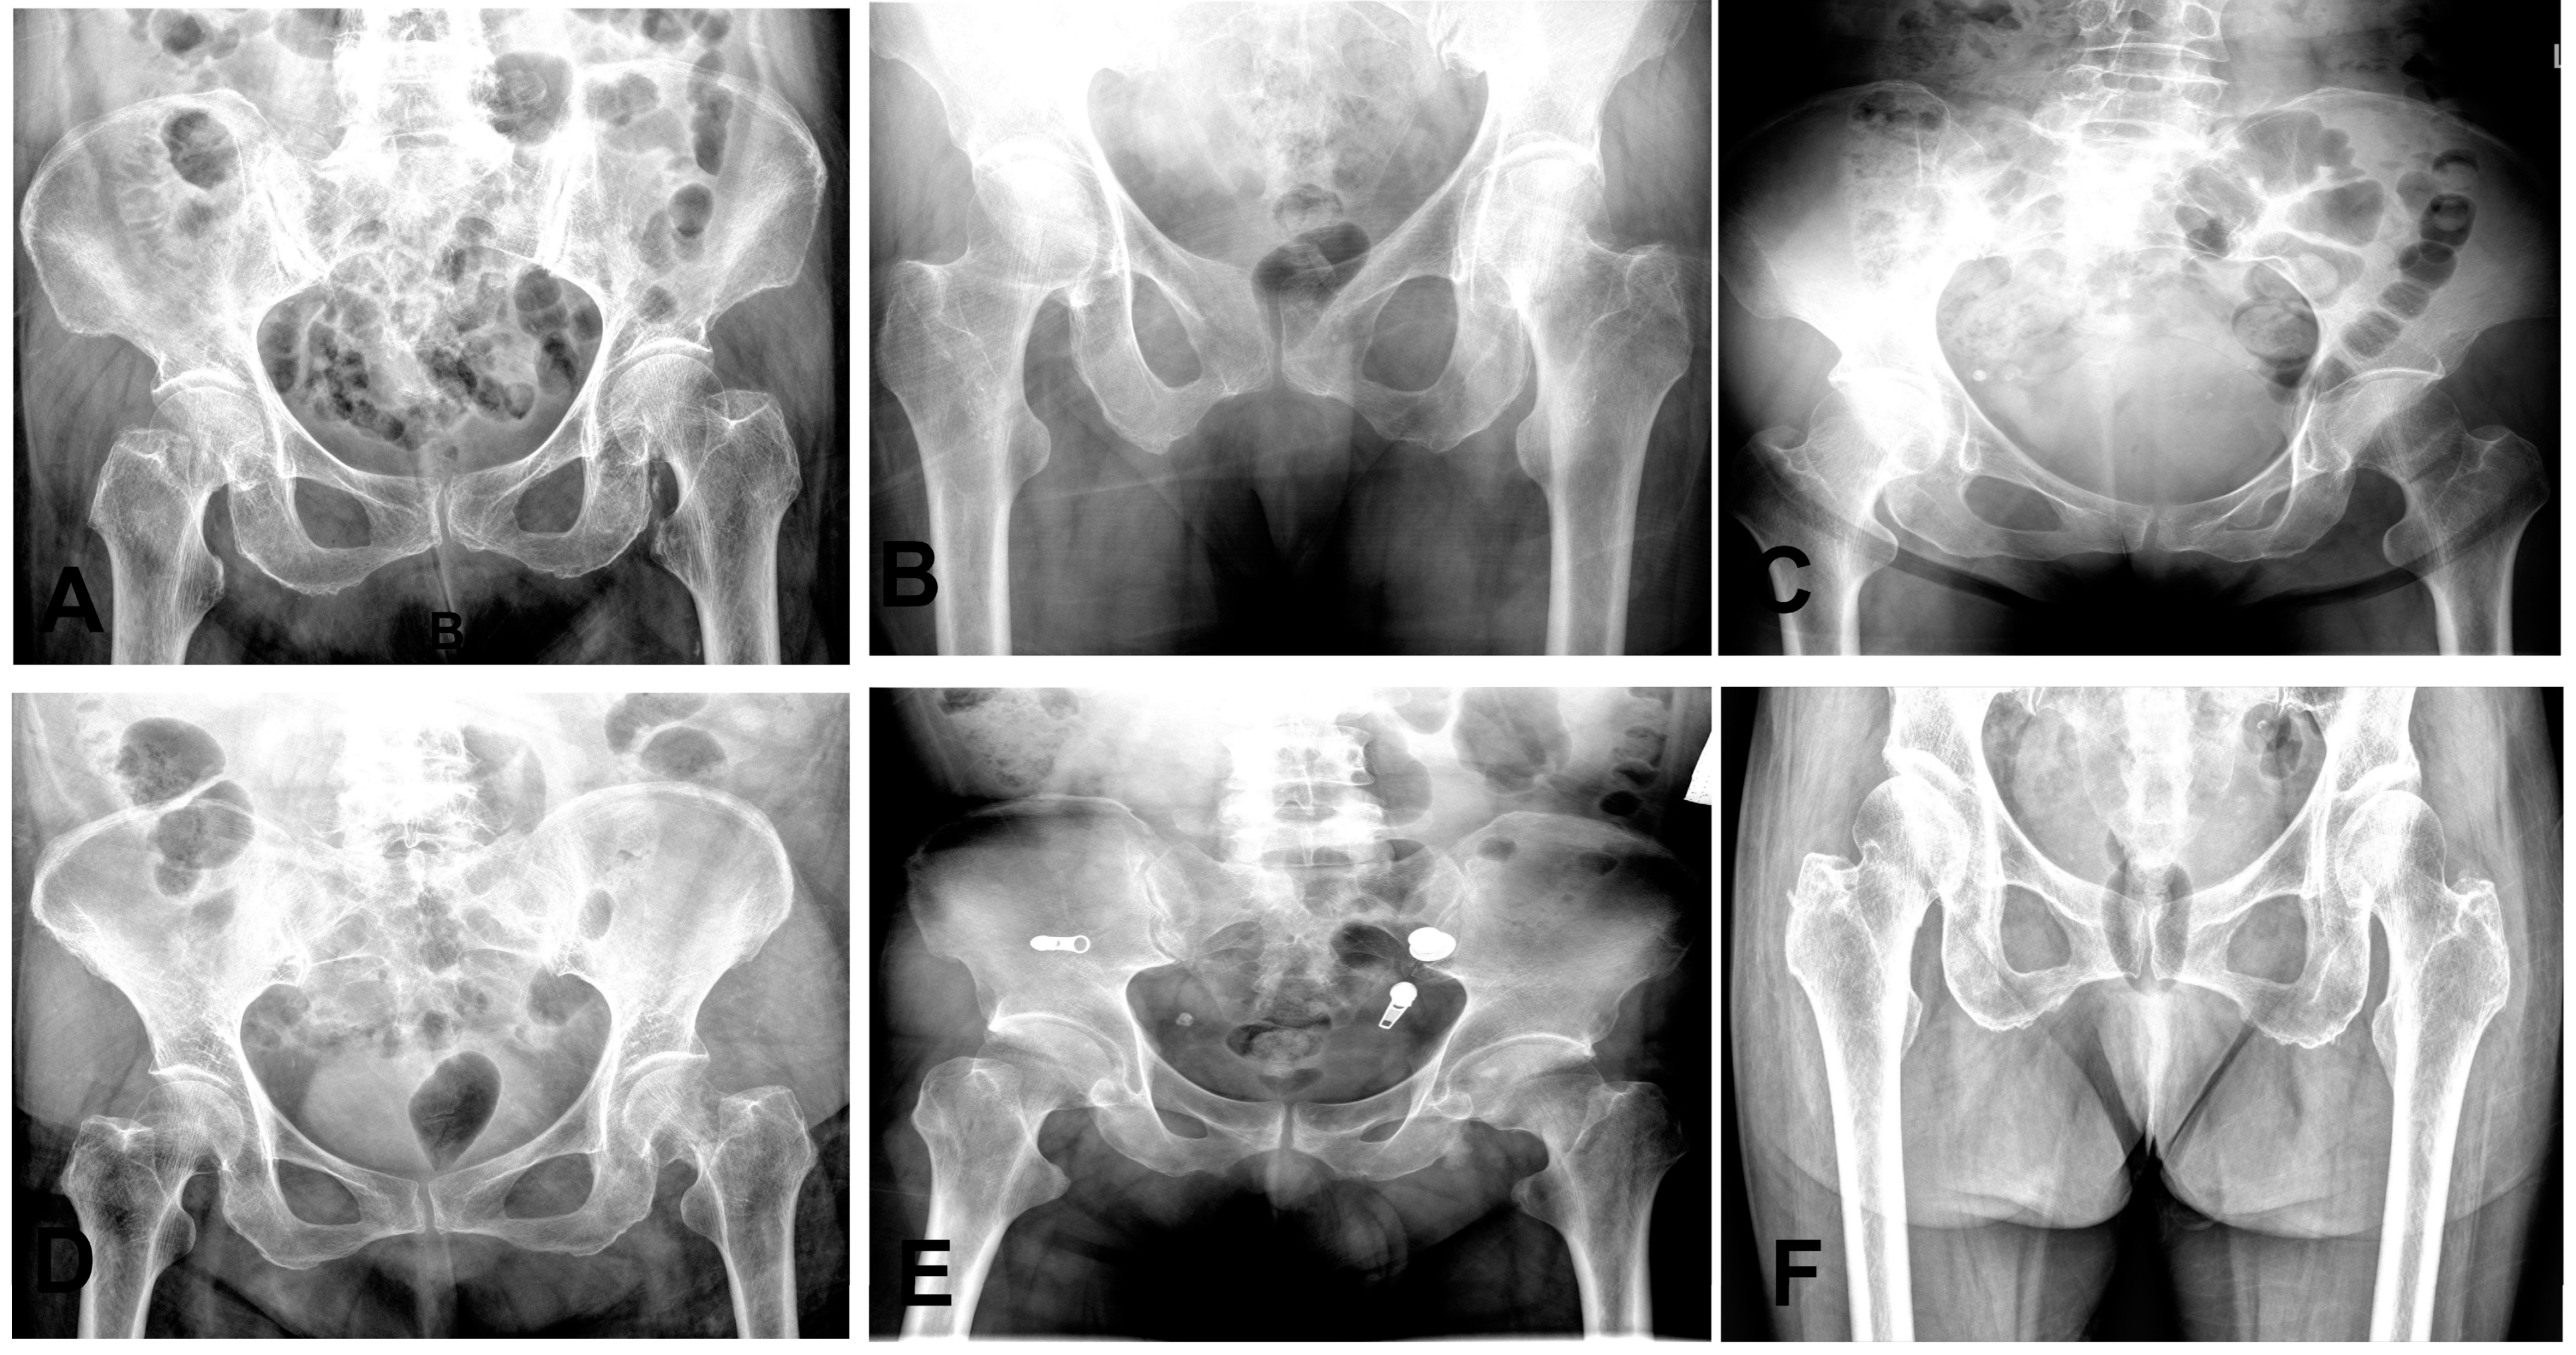

The 95% confidence intervals for both the mean sensitivity and mean specificity of the emergency group were below the ROC curve of the model. We also observed that some cases of fractures were diagnosed as normal by some clinicians, as shown in Figure 7. These results highlight the potential value of our AI model in improving diagnostic accuracy and reducing the risk of misdiagnosis for femoral neck fractures.

Figure 7. Representative radiographs of six nondisplaced femoral neck fractures initially diagnosed as normal on anteroposterior hip X-rays. (A,F): Right hip fractures (two cases). (BE): Left hip fractures (four cases).